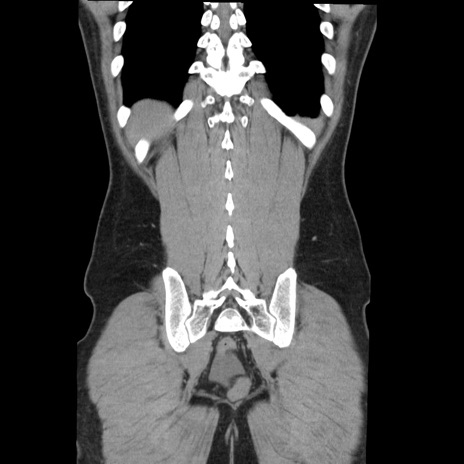

症例36(冠状断像)

【症例】20歳代 男性

【主訴】心窩部痛

【現病歴】今朝より上腹部痛あり。一旦軽快していたが再度出現したため救急要請。昨日夕に白身の魚を含む刺身を食べた。

【身体所見】BP 136/89mmHg、HR 74/min、BT 37.0℃、腹部:膨満、軟、心窩部に圧痛あり。反跳痛なし、筋性防御なし、腸雑音やや亢進あり。

【データ】WBC 17700、CRP 0.48